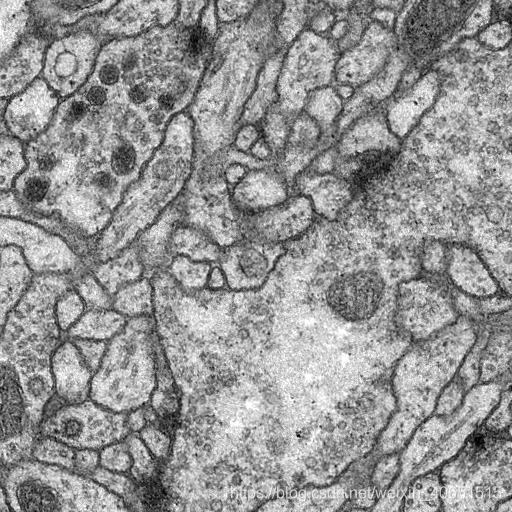

3.1 数据集介绍

数据来自于 ISBI 挑战的数据集。该数据集包含30张训练图、30张对应的标签。30张测试图片。数据是来自果蝇一龄幼虫腹神经索 (VNC) 的串行部分透射电子显微镜 (ssTEM)的图像,其分辨率为4x4x50 nm /像素。

输入原始图像: